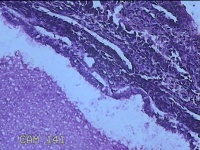

性别

女

年龄

43岁

临床诊断

异常子宫出血

一般病史

月经不规则2年余,发现宫颈赘生物近1年,活检外口可见多个赘生物。

标本名称

宫颈内容物

大体所见

灰白粉红色不规则碎组织1.2x0.8x0.3cm一堆。

图2